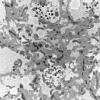

Pompe Disease (4)